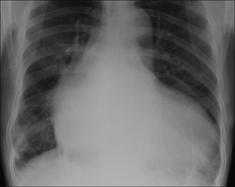

Figure 28.2 Acute dyspnoea. Lungs clear. Both domes of the diaphragm are high. Apply Golden Rule 1—clinical details are crucial. Abdomen is distended with a succussion splash when shaken. CXR conclusion—ascites displacing the diaphragm upwards.